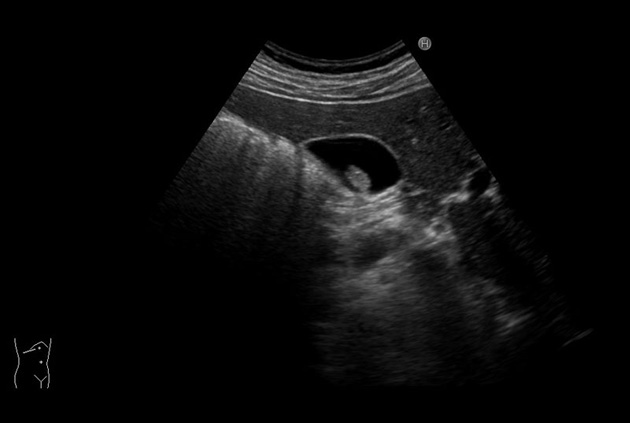

Arietta 70

Recognized for our outstanding image quality, outstanding system reliability and intuitive use of cutting edge technology, Fujifilm Healthcare remains the standard in the field of Surgery.

Learn moreArietta 70

Recognized for our outstanding image quality, outstanding system reliability and intuitive use of cutting edge technology, Fujifilm Healthcare remains the standard in the field of Surgery.